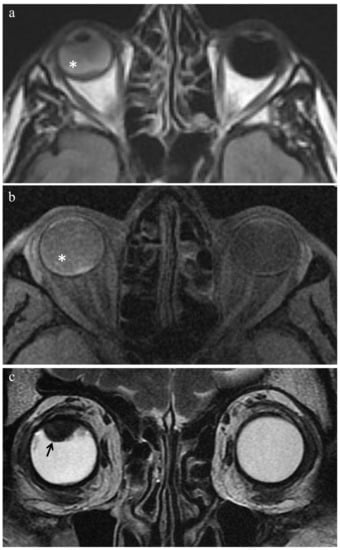

| MR Finding | T2 | T1 | Gd-T1 | DWI |

|---|---|---|---|---|

| Radiation-induced necrosis | ![]() Low signal | ![]() High signal | ![]() No enhancement | ![]() Low signal |

| Fibrosis | ![]() Low signal | ![]() Intermediate signal | ![]() Moderate enhancement | ![]() Low signal |

| Viable tumor tissue, pigmented melanoma | ![]() Low signal | ![]() High signal | ![]() Enhancement of viable tissue | ![]() High signal |

| Viable tumor tissue, poorly pigmented melanoma | ![]() Intermediate signal | ![]() Intermediate signal | ![]() Enhancement of viable tissue | ![]() High signal |

low signal;

intermediate signal;

high signal;

no enhancement;

enhancement of the viable tissue.| MR Finding | T2 | T1 | Gd-T1 | DWI |